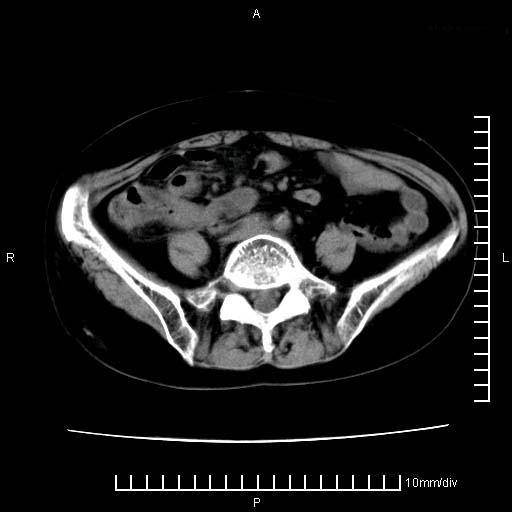

下腹疼痛2月,加重并呕吐2天,下腹压痛,反跳痛。白细胞1万2.

下腹至盆腔较大包块,与邻近肠管关系密切,下腹疼痛2月,加重并呕吐2天,下腹压痛,反跳痛。白细胞1万2.

由于没有做肠道准备很难分清是哪根肠管,但看位置考虑为升结肠回盲部的问题,我首先考虑化脓性阑尾炎,不除外结肠癌合并感染化脓。建议做增强进一步明确。

补充:道格拉斯腔内有积液,且密度较高,显然提示有感染。